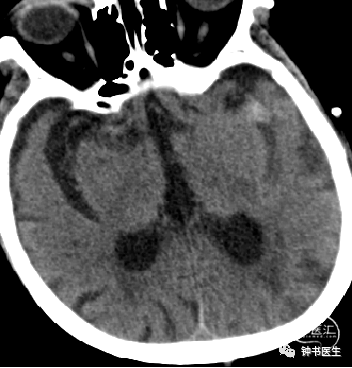

2019-1-13

神经重症治疗思路

血压:90-100mmHg(100-120mmHg)

灌注压:50mmHg(60-70mmHg)

脱水:四联

深度镇静镇痛(咪达唑仑+瑞芬)

ICP:10mmHg以内(1-12mmHg)

2019-1-14

2019-1-16

神经重症治疗思路

血压:90-100mmHg

灌注压:60mmHg

脱水:三联

镇静镇痛(咪达唑仑+瑞芬)

ICP:10mmHg以内

2019-1-19